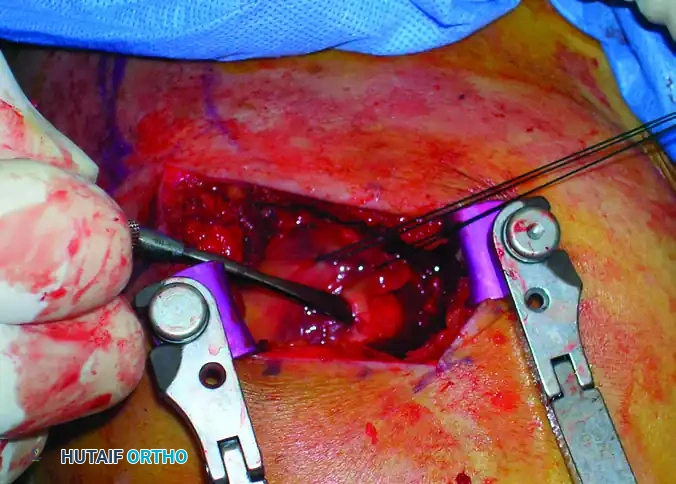

Once the subdeltoid bursa is excised, the rotator cuff footprint is visualized. Under direct observation, incise the supraspinatus tendon in line with its fibers (longitudinally) to access the articular surface of the humeral head.

Place heavy, full-thickness non-absorbable stay sutures (e.g., #2 FiberWire or similar) into the anterior and posterior leaflets of the incised rotator cuff. These sutures serve a dual purpose: they act as retractors to expose the entry point and, crucially, they protect the cuff tissue from being macerated by the reamers during canal preparation.

Intraoperative view showing the deltoid split and the rotator cuff incised and retracted, exposing the proximal humerus.

* Irrigate the subacromial space thoroughly to remove bone debris generated during reaming, which can cause heterotopic ossification.

* Repair the longitudinal split in the supraspinatus tendon using the previously placed heavy non-absorbable sutures. Use a robust, full-thickness figure-of-eight or Mason-Allen suturing technique under direct observation.

Intraoperative view demonstrating the meticulous repair of the rotator cuff with full-thickness sutures following nail insertion.